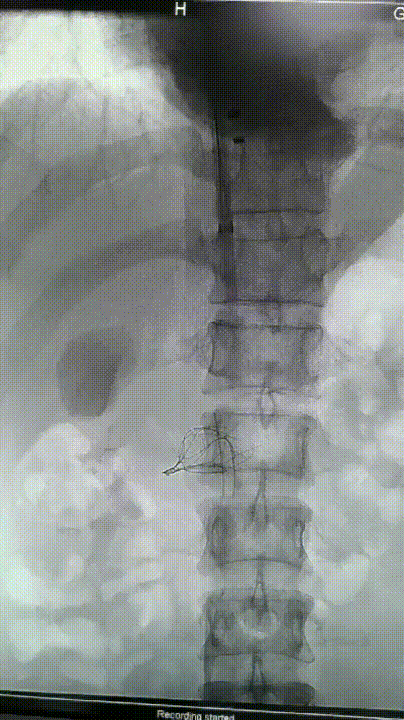

图为:腹腔镜下游离出双侧肾静脉,右侧肾上腺静脉,右侧生殖静脉,下腔静脉近心端上血管吊带

图为:腹腔镜下结扎可见腰静脉,哈巴狗阻断近心端及远心端下腔静脉,可见滤器远端回收勾,此处剪开下腔静脉

图为:腹腔镜直视下抓捕器回收滤器失败